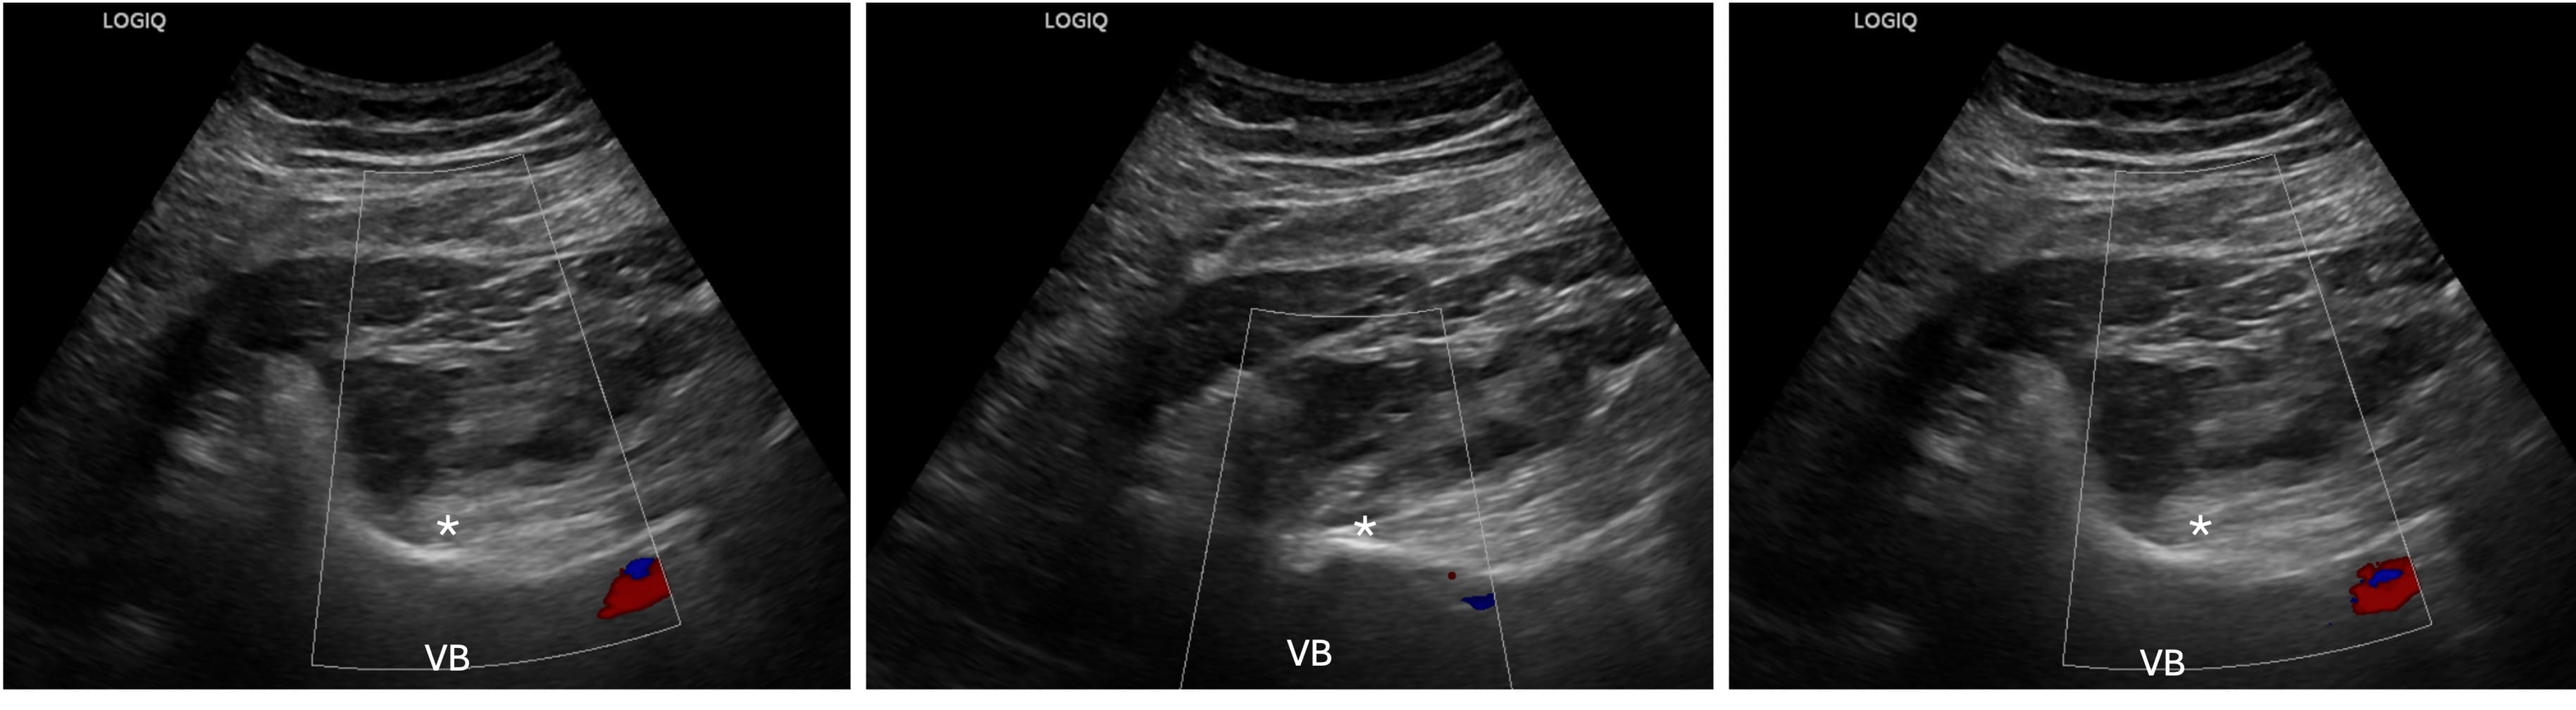

At this point, we aim to optimize a view of the “shamrock sign.” The leaves of the shamrock include the psoas muscle (anteriorly), QL (laterally), and erector spinae muscles (posteriorly), with the transverse process resembling the stem of the shamrock (Figure 2).11 Color Doppler is used to identify the lumbar arteries and plan for a safe needle trajectory (Figure 3).

VB = vertebral body, * = lumbar plexus